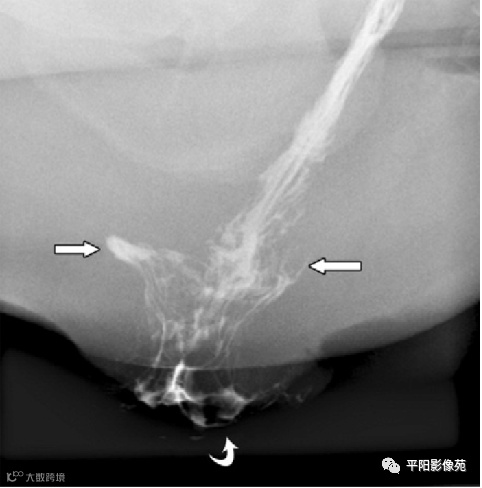

病史:肛周间断性肿物脱出15年,加重伴便血3月

症状:肛周间断性肿物脱出15年,加重伴便血3月,排便

长,大便干结

肛周截石位视诊:3、7、11点痔核环状脱出,血管曲张明显,6点见肛管梭形溃疡。

指诊:肛周6点触痛,未及皮下结节;肛门括约肌收缩良好,齿线附近及痔区粘膜饱满,肛管及直肠未扪及其他肿物,指套无血染,直肠前突明显大于3cm。肛门镜:因疼痛未完成。

排粪造影

直肠壁部分或全层向下移位,称为直肠脱垂(rectal prolapse)

直肠壁部分下移,即直肠黏膜下移,称黏膜脱垂或不完全脱垂

直肠壁全层下移称完全脱垂

排便造影钡(x射线)排便造影或排便直肠造影是诊断排便障碍的公认临床

工具

。

钡排粪造影实时评估直肠壁形态、盆底运动和排空。